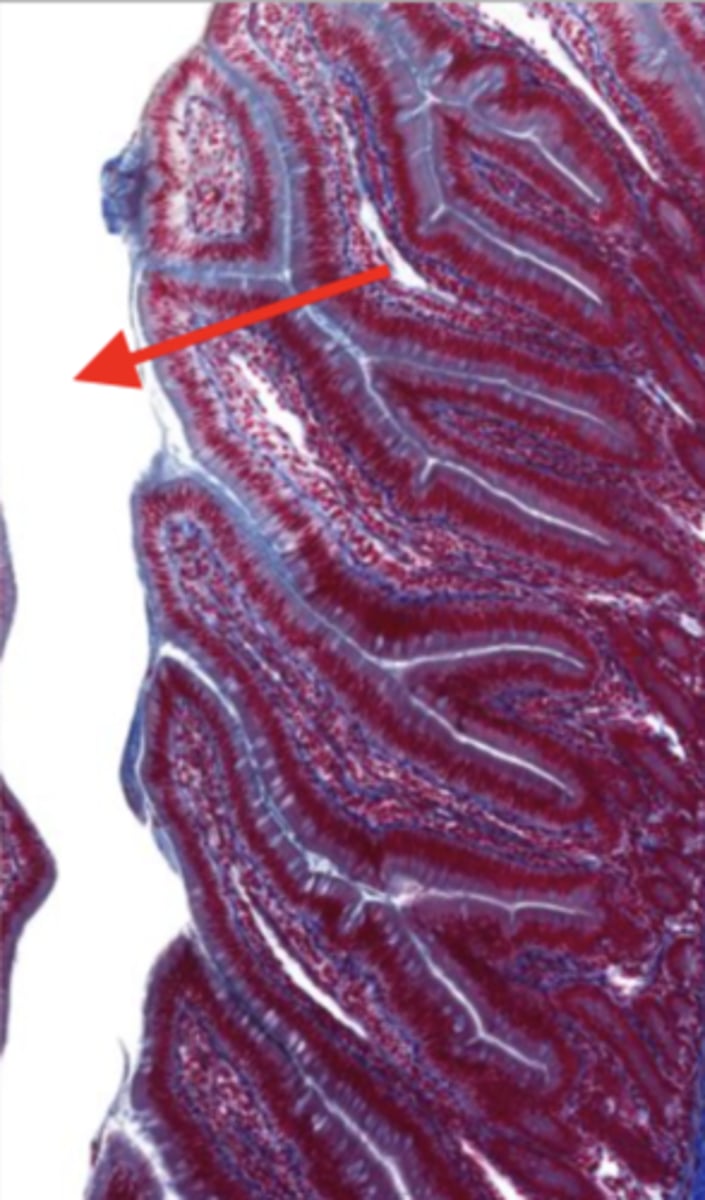

cardiac stomach (histology)

simple columnar epithelium

what kind of epithelium lines the mucosa of the cardiac stomach?

gastric pit (cardiac stomach)

lumen (cardiac stomach)

mucosa (cardiac stomach)

mucosal epithelium (cardiac stomach)

lamina propria (cardiac stomach)

muscularis mucosa (cardiac stomach)

submucosa (cardiac stomach)

contains glands and blood supply

muscularis externa (cardiac stomach)

serosa/adventitia (cardiac stomach)